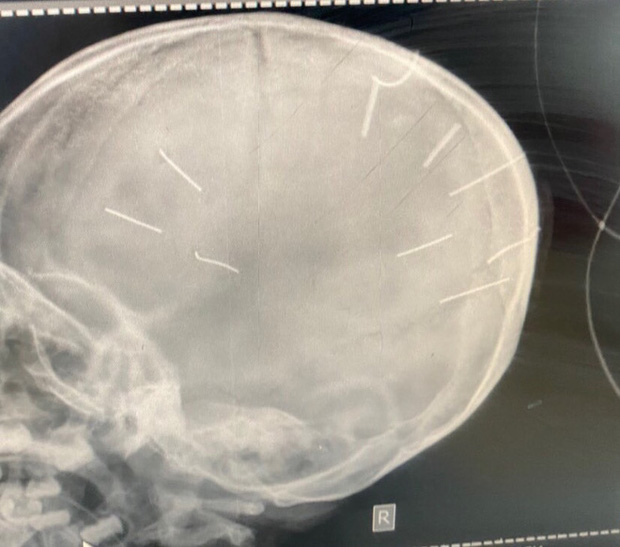

Hình ảnh chụp X-Quang hộp sọ bệnh nhân với 9 hình thể nghi là đinh (Ảnh: Bệnh viện Đa khoa huyện Thạch Thất cung cấp)